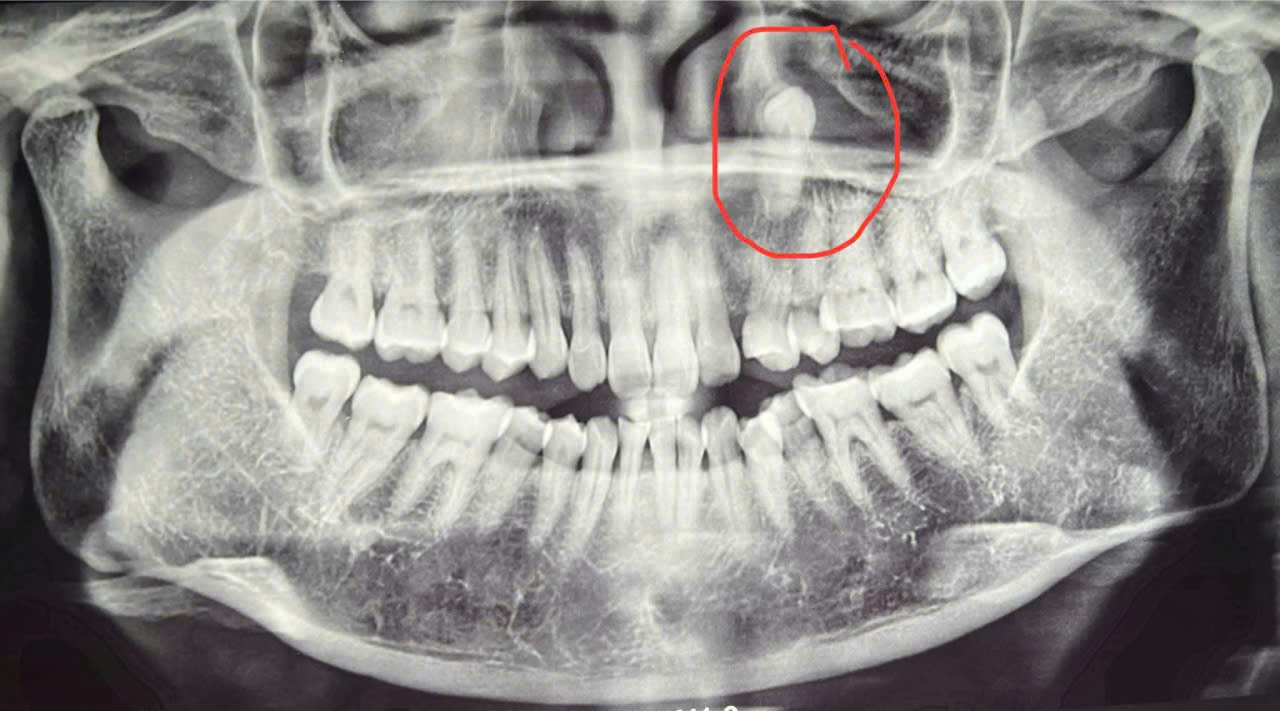

I. ĐỊNH NGHĨA Răng ngầm mọc lạc chỗ là tình trạng răng không mọc đúng vị trí giải phẫu bình thường của nó, thường bị kẹt trong xương hàm hoặc mọc lệch hướng ra ngoài, vào trong, lên trên hoặc xuống dưới so với cung răng. Có thể là răng ngầm hoàn toàn (chưa trồi